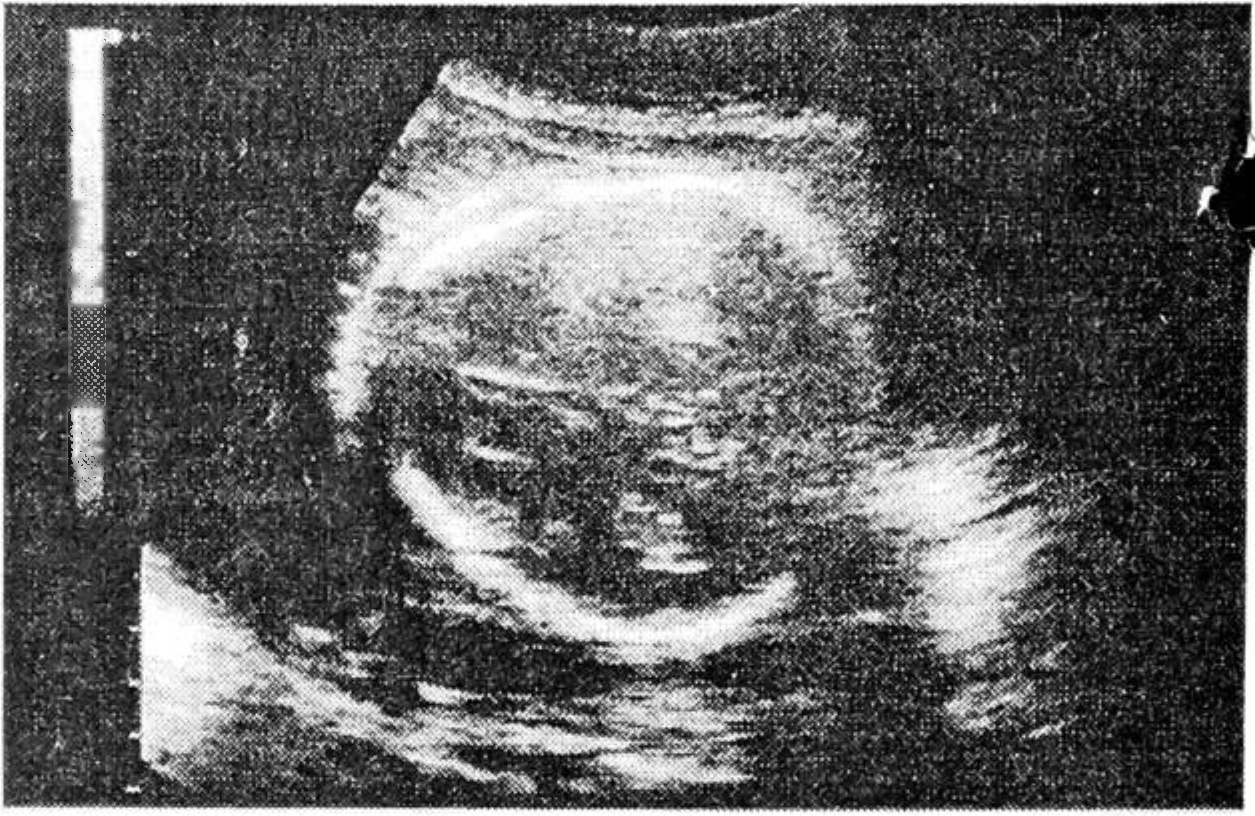

По результатам УЗИ второго этапа: симметричная задержка развития плода, умеренное маловодие, клубникообразная форма головки, гипоплазия лицевого черепа, микрофтальмия (соответствует сроку беременности 24 нед.).

Рис. 1. УЗИ плода (объяснение в тексте).